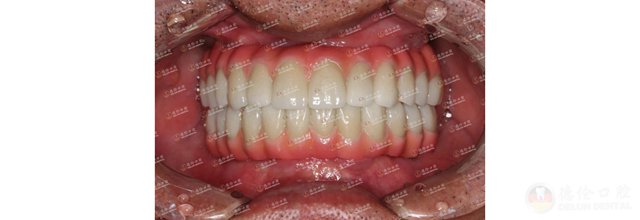

魏女士因牙齿不齐,笑起来不太自信,甚至不愿意笑,想一解烦恼的魏女士选择了德伦口腔东风总院正畸科副主任王苏静进行正畸治疗。嘴凸、牙不齐、薄龈型、且根形明显,王主任在详细检查过魏女士牙齿情况后为其设计了金属自锁的正畸方案,魏女士加入矫牙变美的道路。

魏女士看着自己的牙齿逐渐变得整齐好看,笑起来越来越自信了。回顾矫牙前的自己,笑容始终有一丝放不开,如今在王主任的正畸技术下牙齿逐渐变得整齐,自己的脸型也逐渐变美。

历经23个月,魏女士终于成功“毕业”!魏女士对王主任心怀感激,特意献上一面锦旗,虽然这只是一面简单的锦旗,但这面锦旗饱含的是魏女士心中对王主任的感谢与爱。